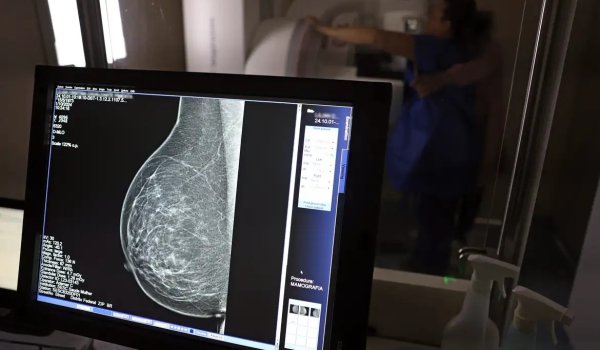

Inca estimou 73.610 novos casos este ano no país

José Cruz/Agência Brasil

No Outubro Rosa, o Instituto Nacional de Câncer (Inca) estimou 73.610 novos casos este ano no país. É o câncer que mais mata mulheres no Brasil. As mulheres em tratamento pela doença têm o direito de receber o auxílio-doença ou o benefício de prestação continuada.